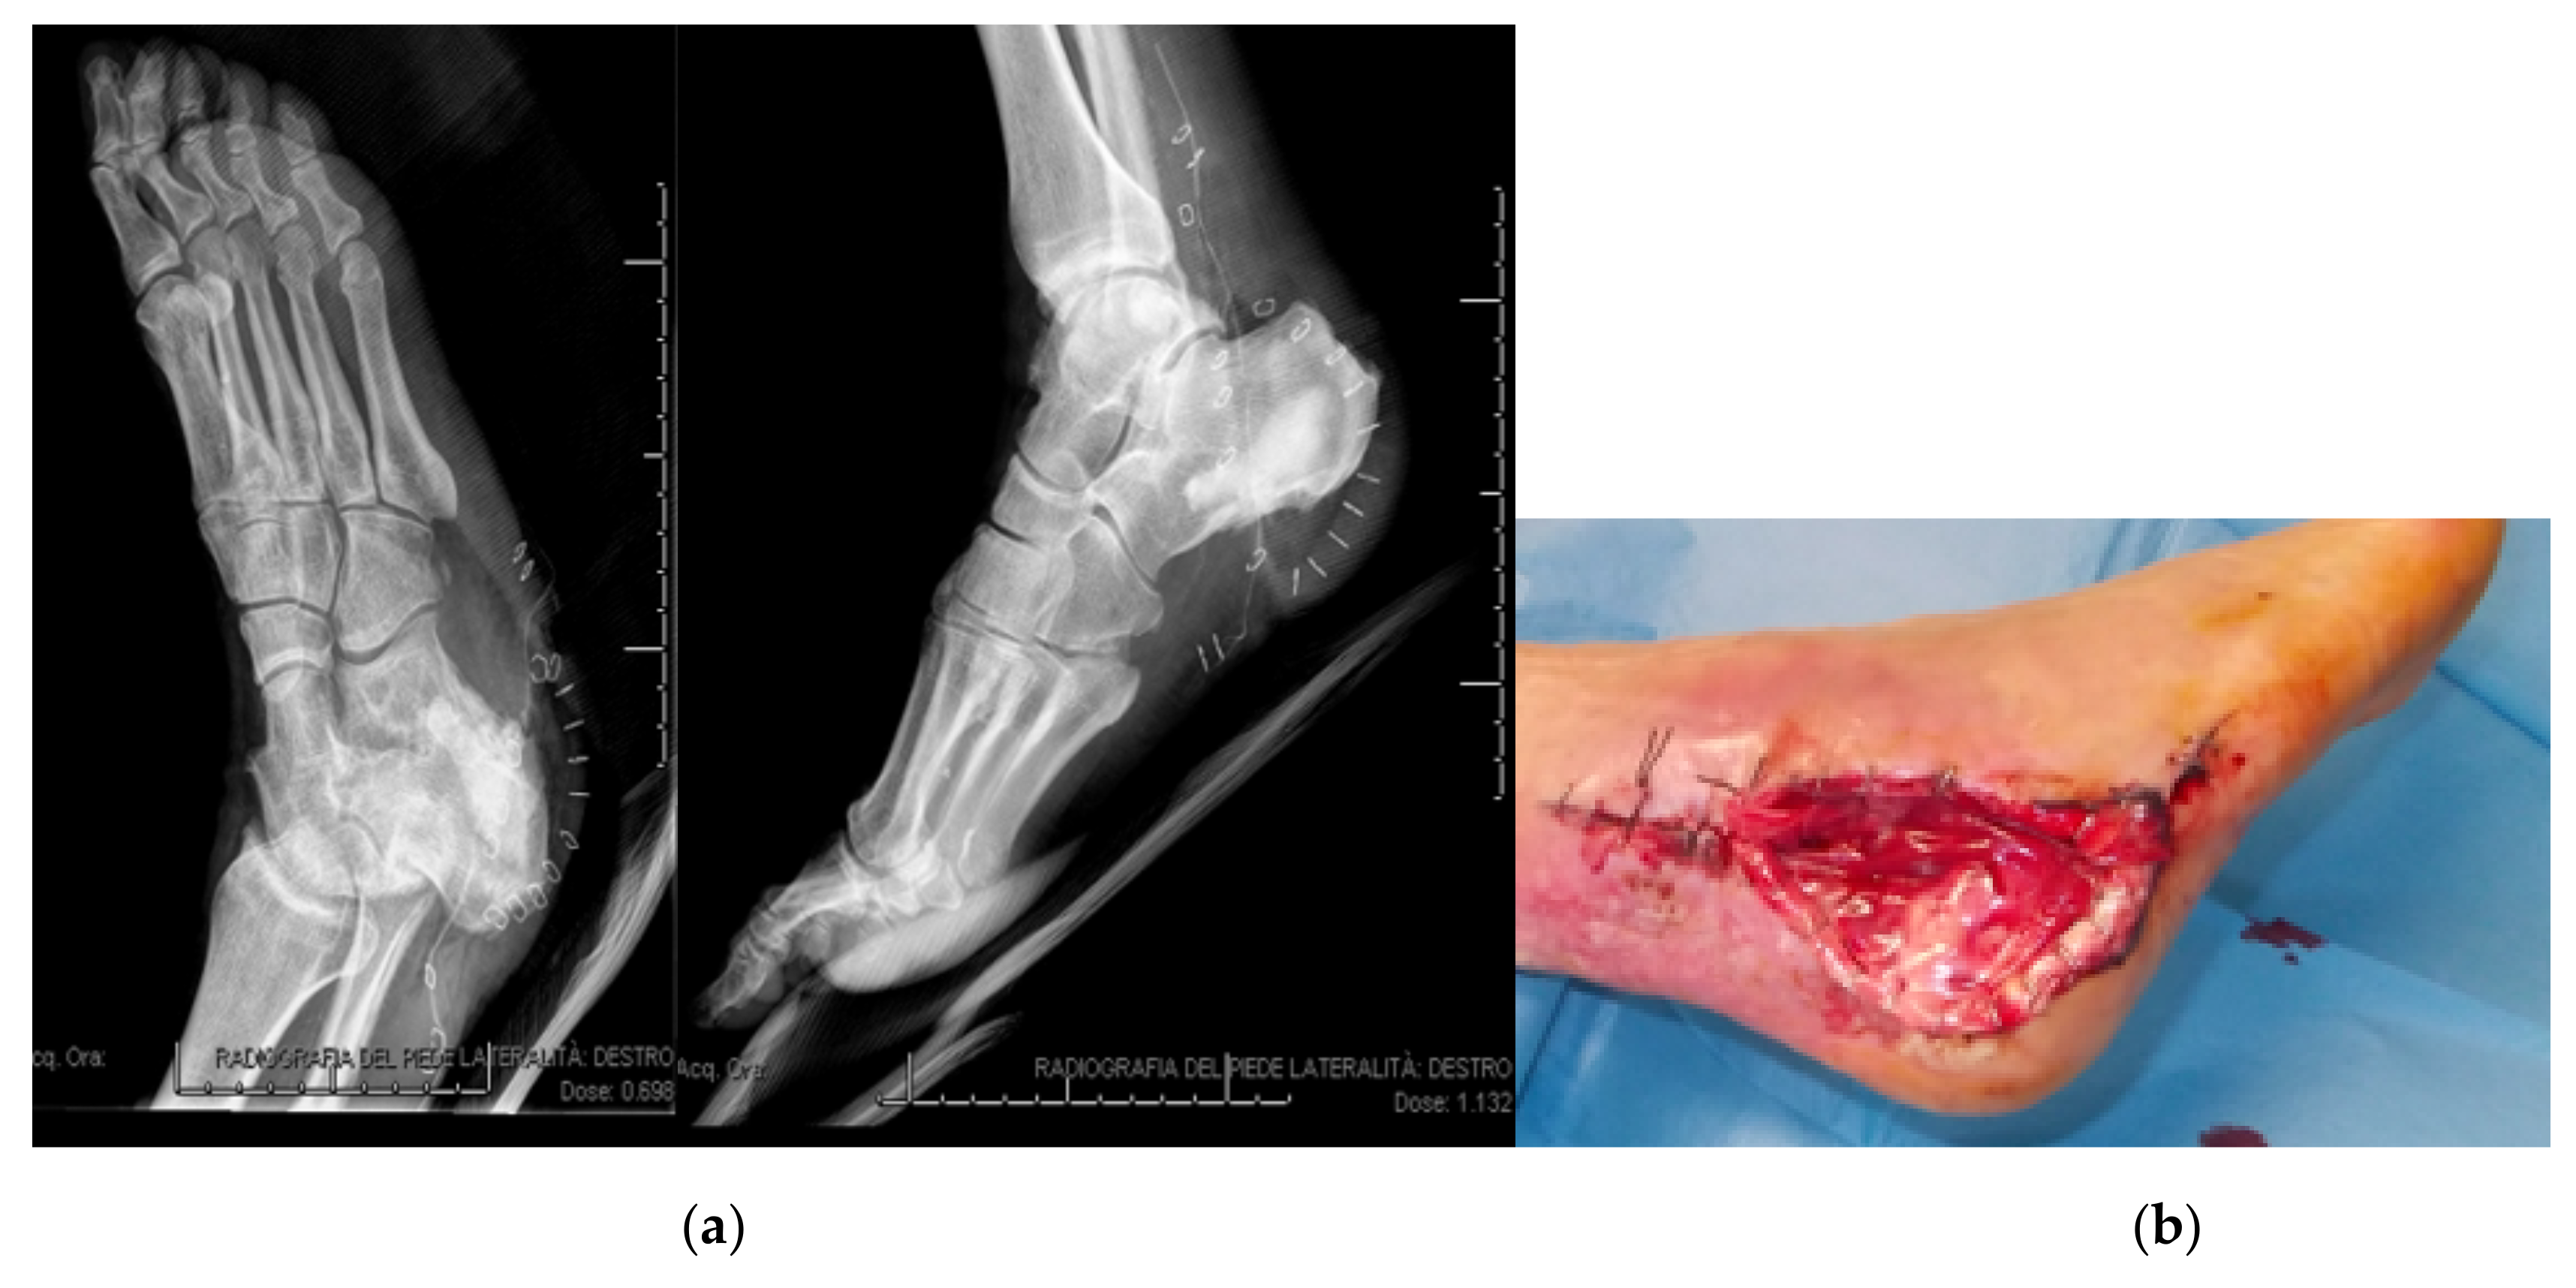

3.1. Calcaneal Lesions